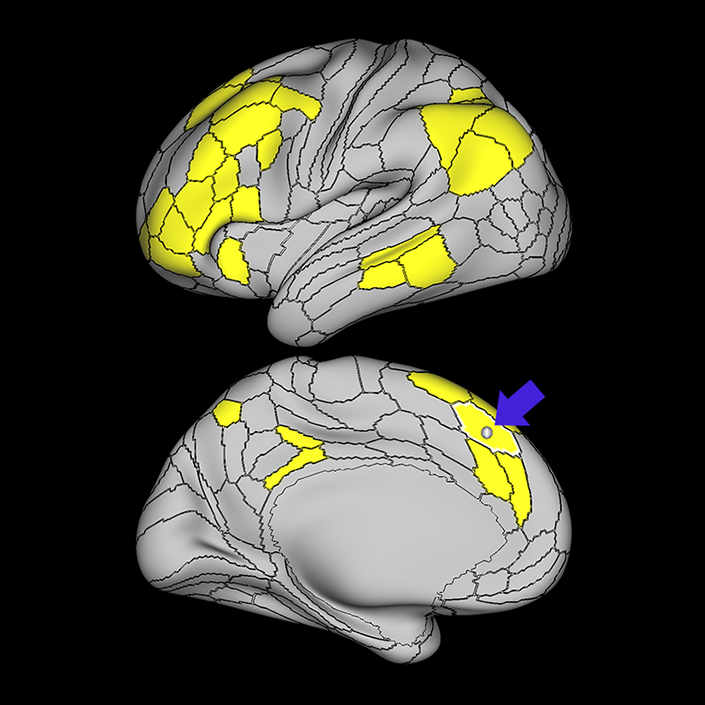

ᐅ SummaryArea PFm (parietal area F, part m): part of the lateral parietal lobe regions. Shows activation in nonspatial attention tasks, decision making when switching choices, rule change during visually guided attention, and reorientation. Also provide syntactical components to language processing, plays a role in attentional processing, and is activated in working memory, motor cue, and risk-related tasks. ᐅ Where is it?Area PFm (parietal area F, part m) is found on the anterior superior surface of the angular gyrus, and straddles the sulcus to lie on the posterior superior bank of the supramarginal gyrus. ᐅ What are its borders?Area PFm borders IP2 and IP1 superiorly, PF anteriorly, PSL and STV inferiorly, and PGI and PGS posteriorly. ᐅ What are its functional connections?Area PFm demonstrates functional connectivity to areas 8AV, 8AD, 8BL, 8C, s6-8, i6-8, a47r, p47r, a10p, p10p, 9a, a9-46v, p9-46v, and area 44 in the lateral frontal lobe, area d32 in the medial frontal lobe, area AVI in the insula, areas STSvp, TE1m, TE1p, and TE2a, in the temporal lobe, areas PGs, PGi, IP2, and IP1 in the lateral parietal lobe, and areas 7m, 7pm, POS2, 31a, 31pv, d23ab, 23d and RSC in the medial parietal lobe. ᐅ What are its white matter connections?Area PFm is structurally connected to the arcuate/SLF. Arcuate/SLF connections course anteriorly from PFm to 8C and 8BM, and inferiorly to middle temporal gyrus parcellations TE1a, TE1m, TE1p, STSva, STSvp and PHT. Local short association bundles connect with AIP, 7PC, IP1, IP2, LIPd, LIPv, PGi, PGs, 2 and 1 ᐅ What is known about its function?PFm shows activation in non-spatial attention tasks, decision making when switching choices, rule change during visually-guided attention, and reorientation. Intermediate regions of the inferior parietal lobule also provide syntactical components to language processing. This area also plays a role in attentional processing, and is activated in working memory, motor cue, and risk-related tasks. |

A: lateral-medial

B: anterior-posterior

C: superior-inferior

DTI image |